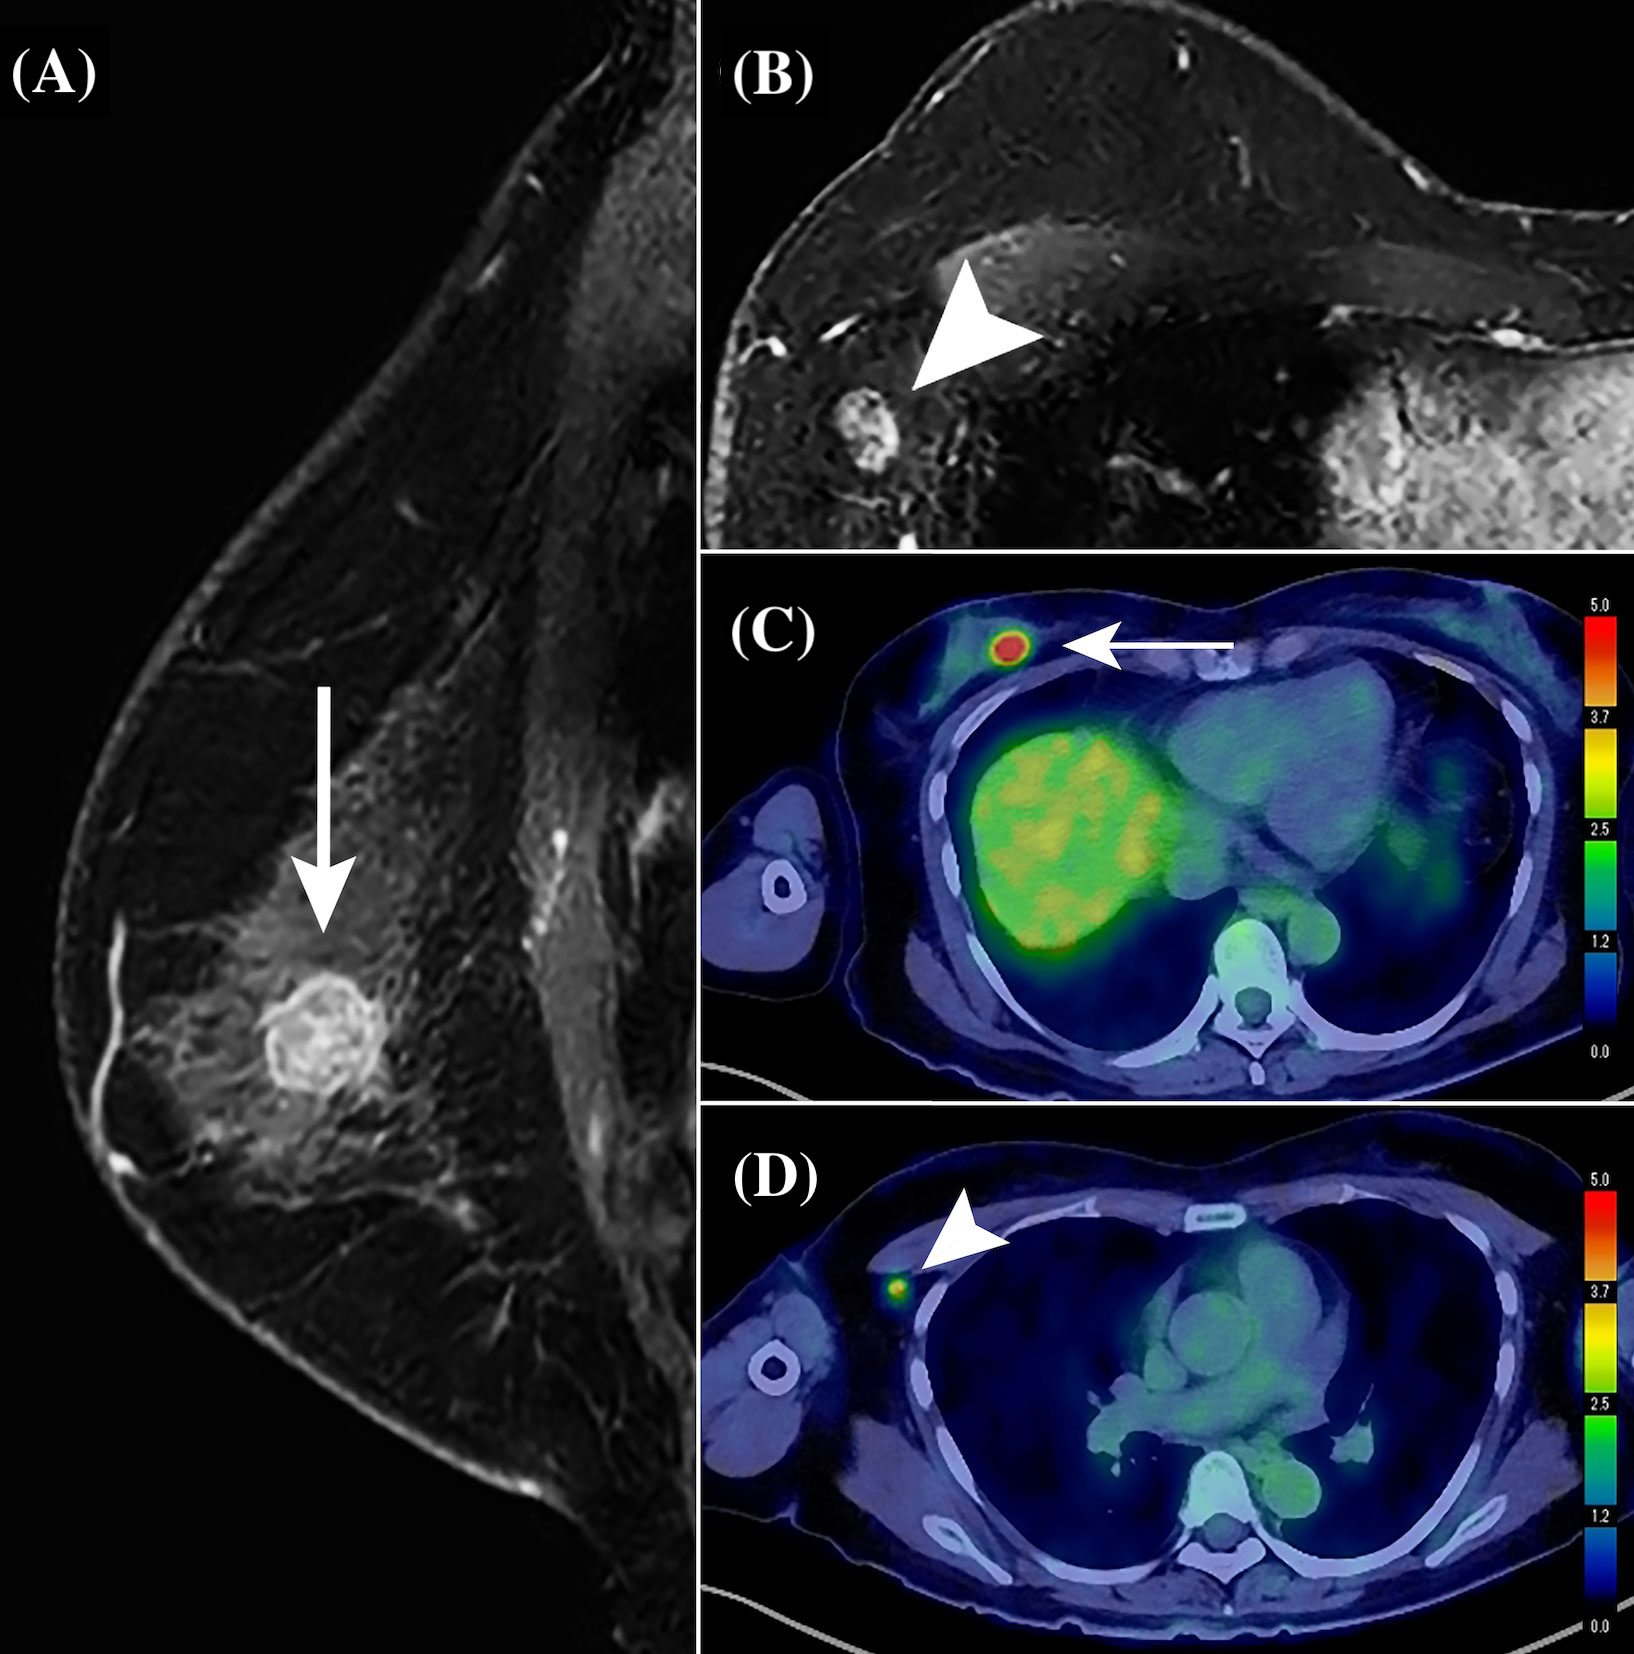

Facilitate learning with our scientific Pet/ct Lymphatic System gallery of hundreds of educational images. accurately representing photography, images, and pictures. perfect for research publications and studies. Browse our premium Pet/ct Lymphatic System gallery featuring professionally curated photographs. Suitable for various applications including web design, social media, personal projects, and digital content creation All Pet/ct Lymphatic System images are available in high resolution with professional-grade quality, optimized for both digital and print applications, and include comprehensive metadata for easy organization and usage. Explore the versatility of our Pet/ct Lymphatic System collection for various creative and professional projects. Multiple resolution options ensure optimal performance across different platforms and applications. Whether for commercial projects or personal use, our Pet/ct Lymphatic System collection delivers consistent excellence. Professional licensing options accommodate both commercial and educational usage requirements. Each image in our Pet/ct Lymphatic System gallery undergoes rigorous quality assessment before inclusion. Time-saving browsing features help users locate ideal Pet/ct Lymphatic System images quickly. Advanced search capabilities make finding the perfect Pet/ct Lymphatic System image effortless and efficient. Comprehensive tagging systems facilitate quick discovery of relevant Pet/ct Lymphatic System content. Instant download capabilities enable immediate access to chosen Pet/ct Lymphatic System images.